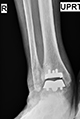

During an appointment with Dr. Vann, an evaluation will include a review of the individuals history, discussion of current symptoms, physical examination, x-rays, a discussion of findings and treatment options.

Our standing xray protocol is used to determine the overall shape, structure and integrity of the ankle and foot, while facilitating a comparison with the opposite side. The x-rays also assist in the evaluation of associated conditions.